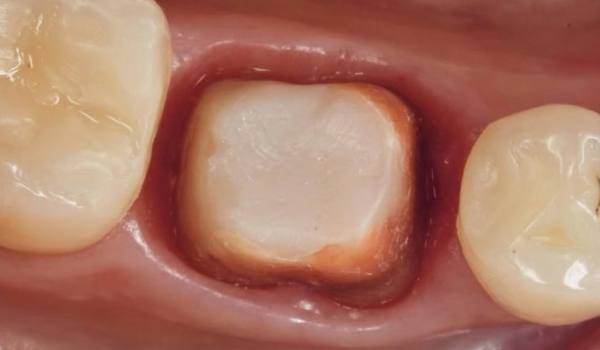

✅ Протокол лікування. Клінічні приклади

• Вертикальне препарування, полірування

• Зона фінішної лінії

• Контроль кровотечі